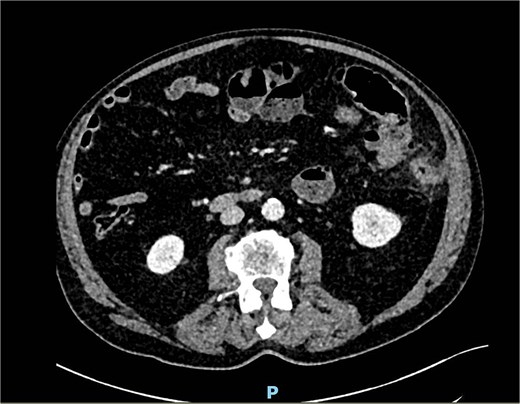

A computed tomography angiography (CTA) of the abdomen was performed, it showed a long segment of the small bowel with wall thickening in the right lower quadrant, accompanied by a inflammatory change in the mesenteric fat with multiple air bubbles, and free fluid in the pelvis, suggestive of hollow organ perforation (Fig. 1). Given the high suspicion of hollow organ perforation and clinical signs of peritonitis, an indication for exploratory laparotomy was established and performed as an emergency procedure. An antibiotic therapy with piperacillin/tazobactam was empirically initiated preoperatively.

CTA showing a long segment of small bowel with inflammatory wall thickening and fat stranding of the mesentery with multiple air bubbles.